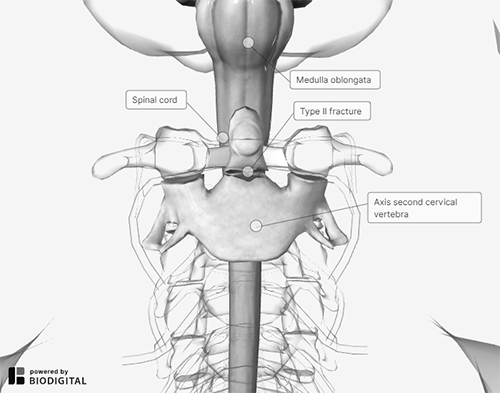

In very young patients (younger than 10 years of age), the fracture typically occurs at the site of the basilar synchondrosis. Odontoid fractures are the most common fractures of the atlas and account for nearly 15% of all cervical fractures.29 Similar to evaluation of an OO, a detailed neurologic exam is vital when evaluating an odontoid fracture. (See Figure 3.)

Figure 3. Odontoid (Dens) Fracture |

|

Courtesy of BioDigital. |